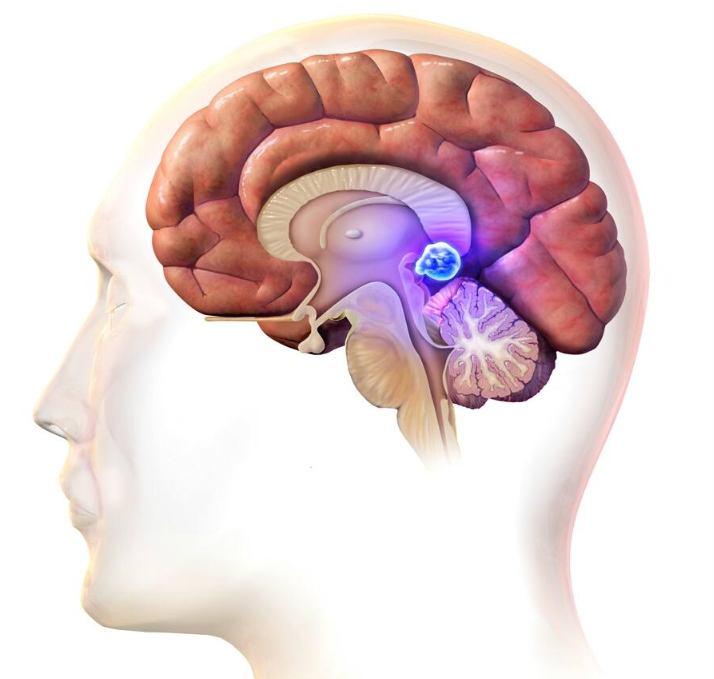

Tuyến tùng là một tuyến nội tiết nhỏ nằm trong não của các loài động vật có xương sống gần trung tâm não bộ có chức năng giúp điều chỉnh nhịp sinh học.

U tuyến tùng là khối u nằm ở vùng này bao gồm u của tuyến tùng và u các thành phần, cấu trúc của vùng này. Khối u tuyến tùng có thể chèn ép não thất III, chèn ép cống não gây não úng thủy, chèn ép cuống não trên, chèn ép tiểu não, chèn ép hố sau... gây nên các rối loạn khác nhau.